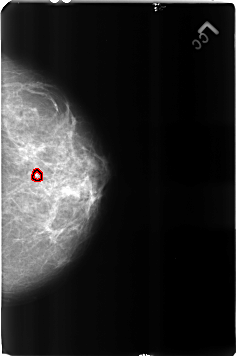

FILE: B_3160_1.LEFT_CC.OVERLAY

TOTAL_ABNORMALITIES 1

ABNORMALITY 1

LESION_TYPE CALCIFICATION TYPE LUCENT_CENTERED DISTRIBUTION N/A

ASSESSMENT 2

SUBTLETY 4

PATHOLOGY BENIGN

TOTAL_OUTLINES 1

BOUNDARY